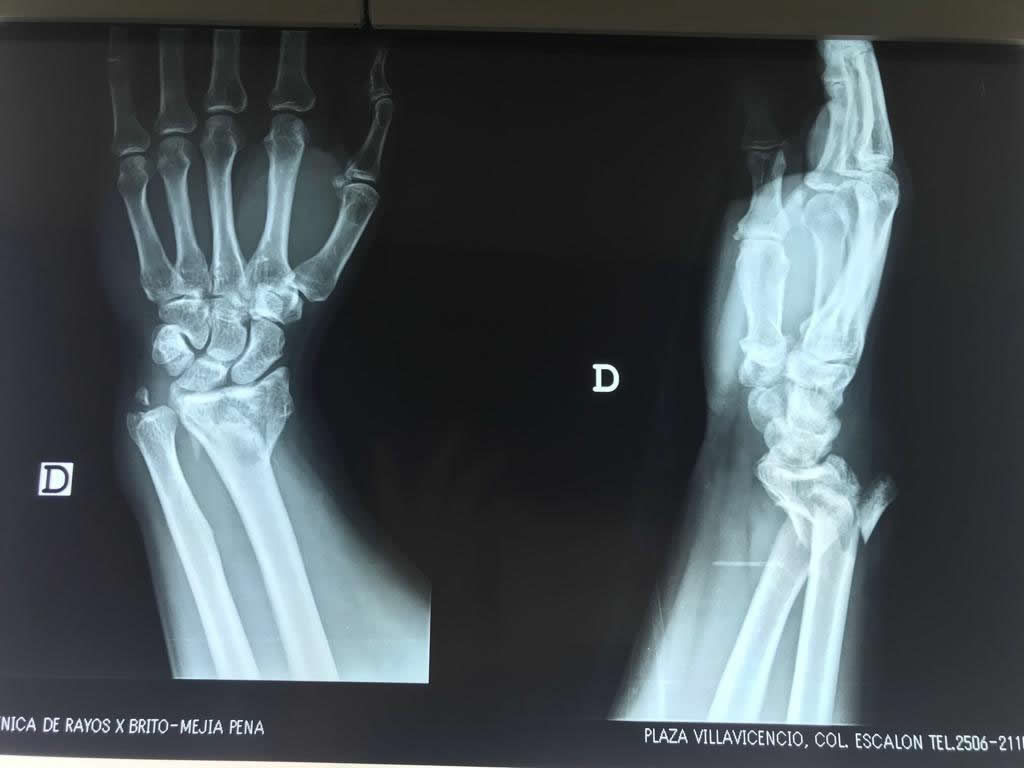

Cirugías de Húmero - Cirugías de Muñecas y Manos

Los procedimientos más comunes en cirugía de la mano son aquellos destinados a reparar traumatismos, incluyendo lesiones de tendones, nervios, vasos sanguíneos, y articulaciones; huesos fracturados; y quemaduras, cortes, y otros daños de la piel.